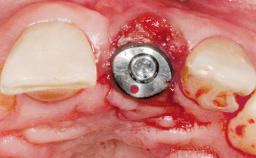

Immediate Placement of an Implant in a Maxillary Left Central Incisor Site

A 33-year-old female patient presented with an upper left central incisor that required extraction after a failed endodontic therapy. The tooth had been traumatized when the patient was a teenager and had undergone several endodontic treatments, including two apicectomy procedures. The patient was in good health and did not smoke. Clinical examination showed that the patient had a high lip line. In full smile, the gingival margins of the upper teeth were visible to the first molars. The gingival margins of central incisors 11 and 21 were only just showing. Examination of tooth 21 confirmed that the tooth was mobile and had hypererupted by 1 mm.

Placement Protocol Immediate implant placement

Tooth Site Maxillary incisor or canine

Socket Morphology Single-root socket

Socket Integrity Damage to one or more bone walls

Bone Volume Damage to one or more socket walls

Bone Augmentation Horizontal|Simultaneous

Soft Tissue Grafting Simultaneous